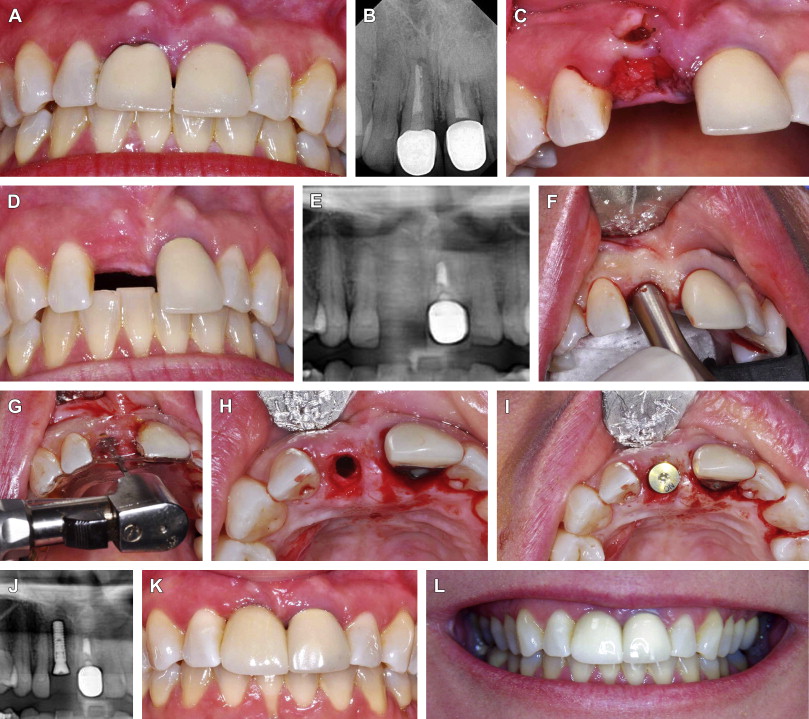

Immediate implant placement in fresh extraction sockets using the open Sponge In Tooth Socket I found out that my oral surgeon put a collagen plug in the socket. Etik collagene is recommended in patients on antithrombotic medication (such as. I recently had a tooth extracted — it was non wisdom. Antimicrobial agent containing absorbable gelatin sponge to prevent dry socket: The purpose of this study was to compare the effectiveness of absorbable collagen. Etik. Sponge In Tooth Socket.